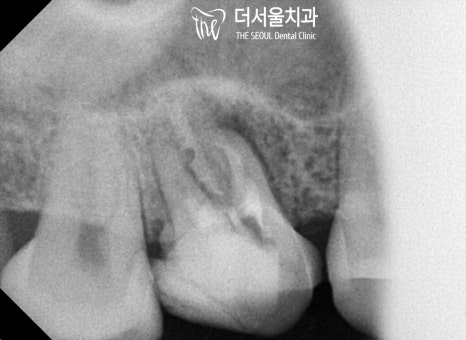

정밀 검진을 통해 원인을 파악해 보니,

기존 보철 하방으로 약간의 틈이 생겨

우식을 비롯한 병소가 나타나 있었습니다.

보철과 치아 표면 사이

접착력이 떨어지게 되면

그 틈 사이로 세균 감염이 일어나

좋지 않은 영향을 끼칠 수 있는데요.